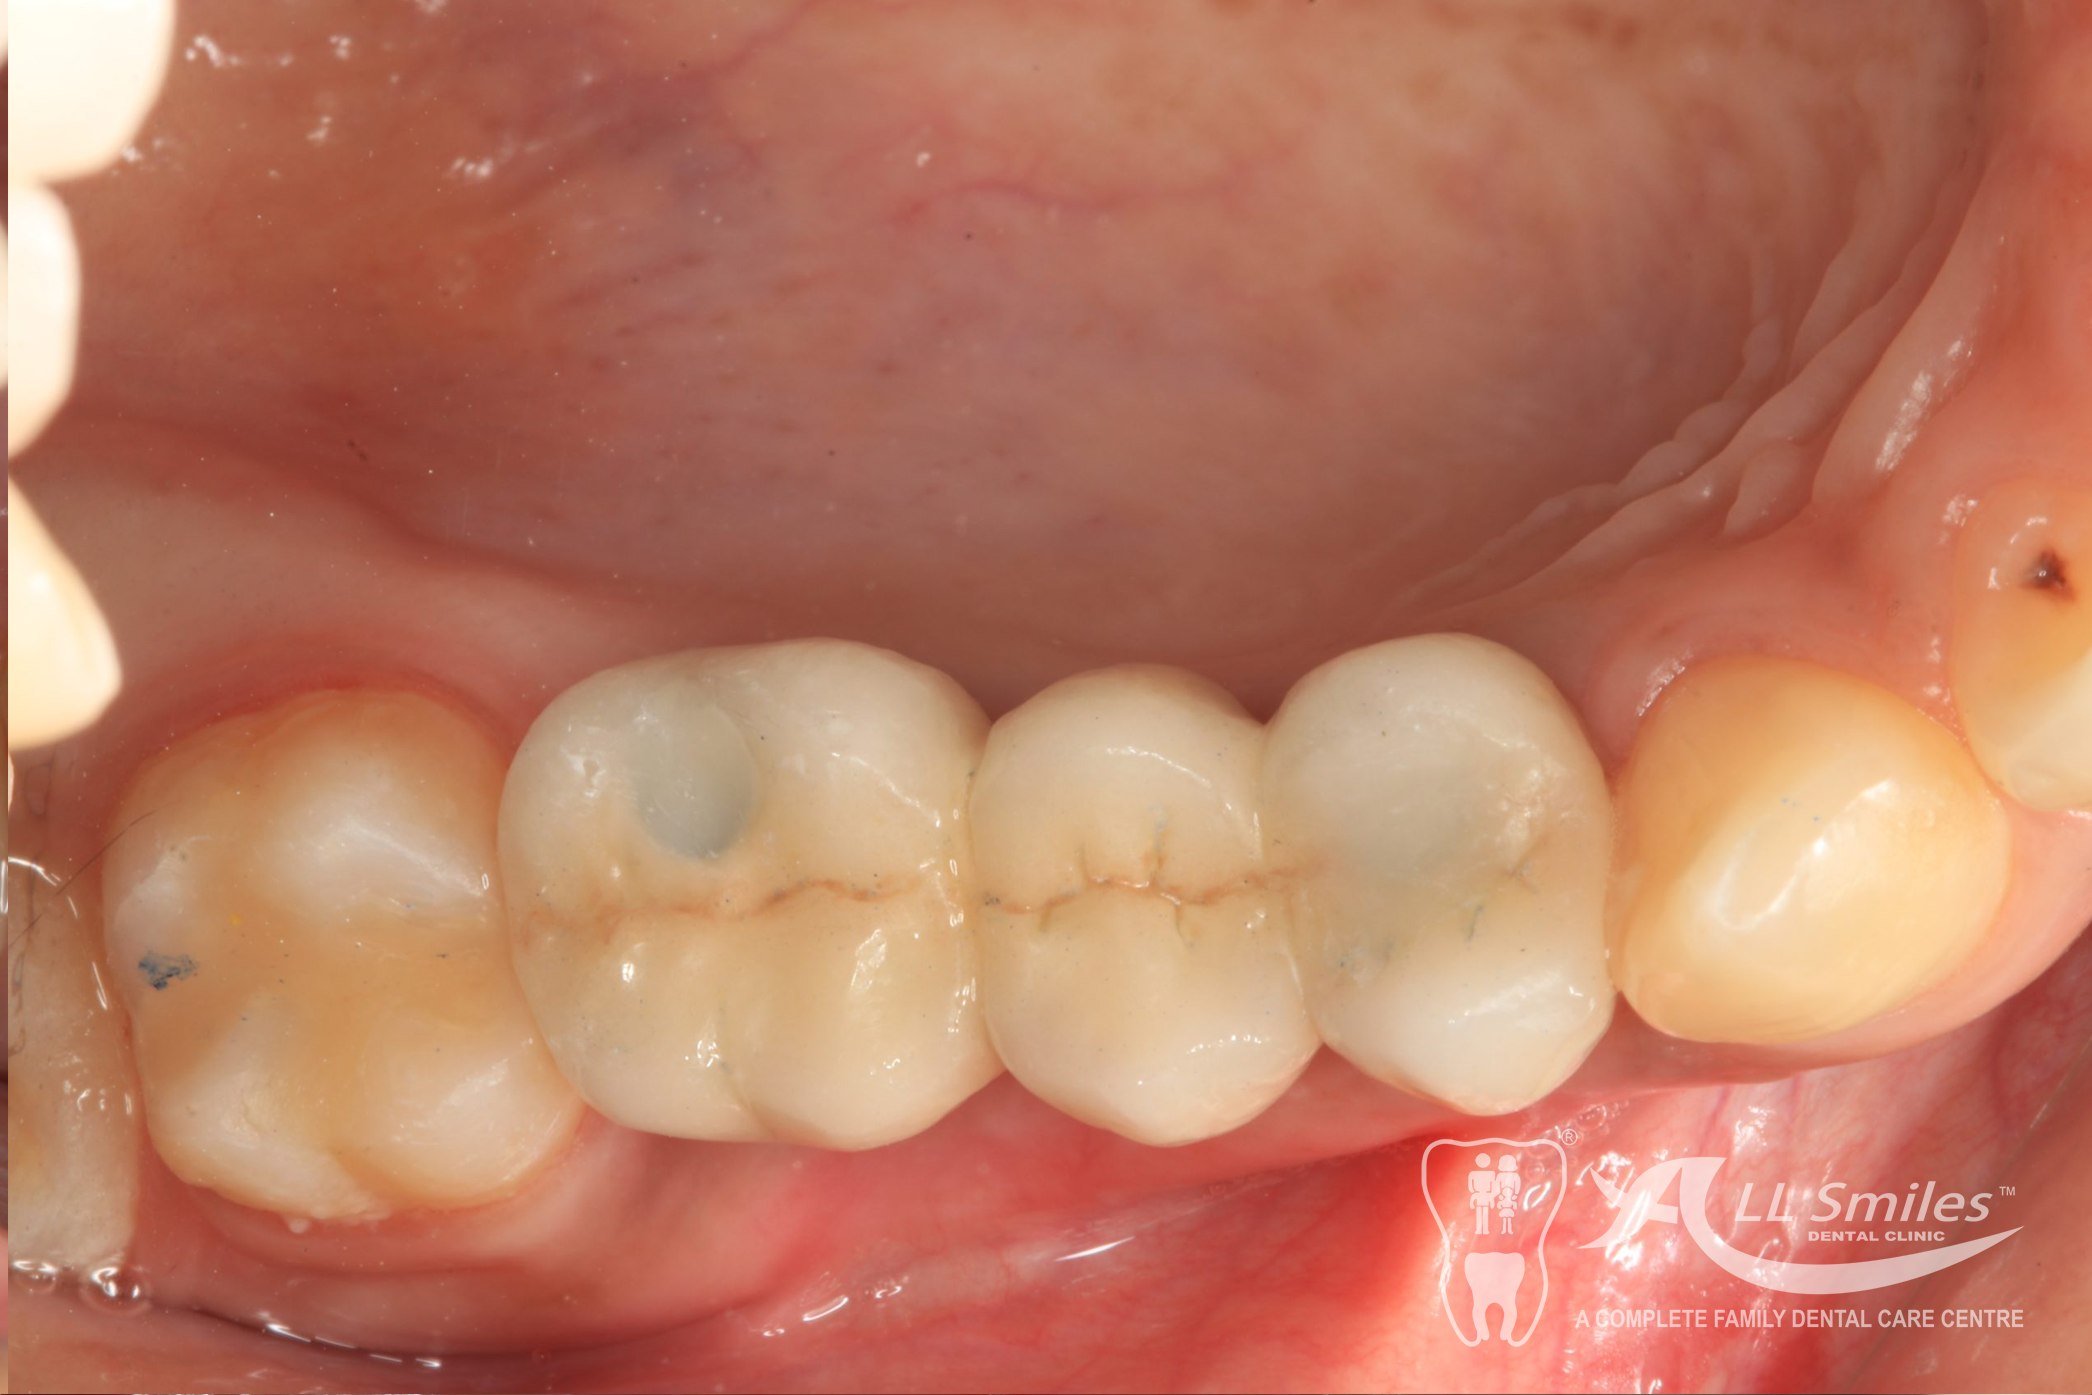

This usually does not take any longer than any routine treatment. A temporary restoration closes the gap until the implant is healed. Then the final tooth crown is fixed in place – permanently . With the new root it is fixed firmly in the jaw and feels identical to your natural teeth.

Implants For Multiple Missing or Broken Teeth Regardless of whether one or more teeth are missing in a row: Every tooth is individually replaced and the situation is restored to its original condition. If three or more teeth in a row are missing, you can decide to have an implant- borne bridge. In this solution the new crowns are linked together and depending on the size of the gap are placed on a stable and secure base of two or more implants .

After precise planning the new tooth roots are generally placed in the jaw in one single treatment session. A temporary denture closes the gaps during the healing phase. After healing the final crowns or the bridge are permanently fixed to the implants. Life With Bite! Dental Implants For The Edentulous Jaw.